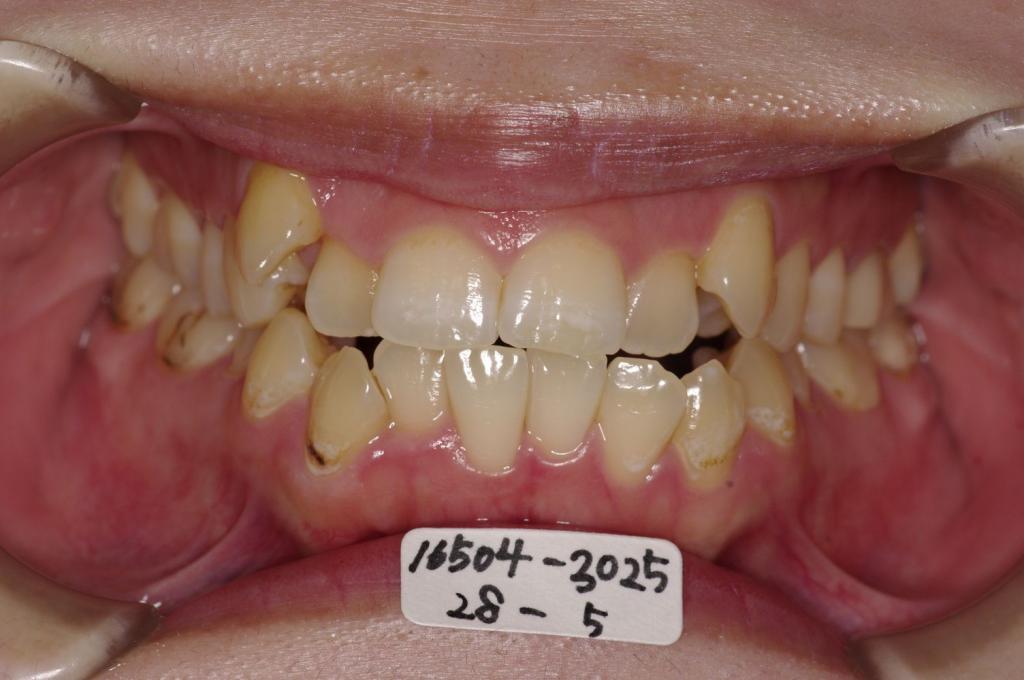

前歯、出っ歯・開咬の矯正治療

(治療期間、治療前後写真、治療方法、費用)WORKS

下記の実績データをクリックして頂くと「性別」、「治療開始年齢」、「治療終了年齢」、「治療方法(矯正治療装置写真含む)」、「治療終了までの費用」など、詳細な矯正治療データをご覧頂けます。